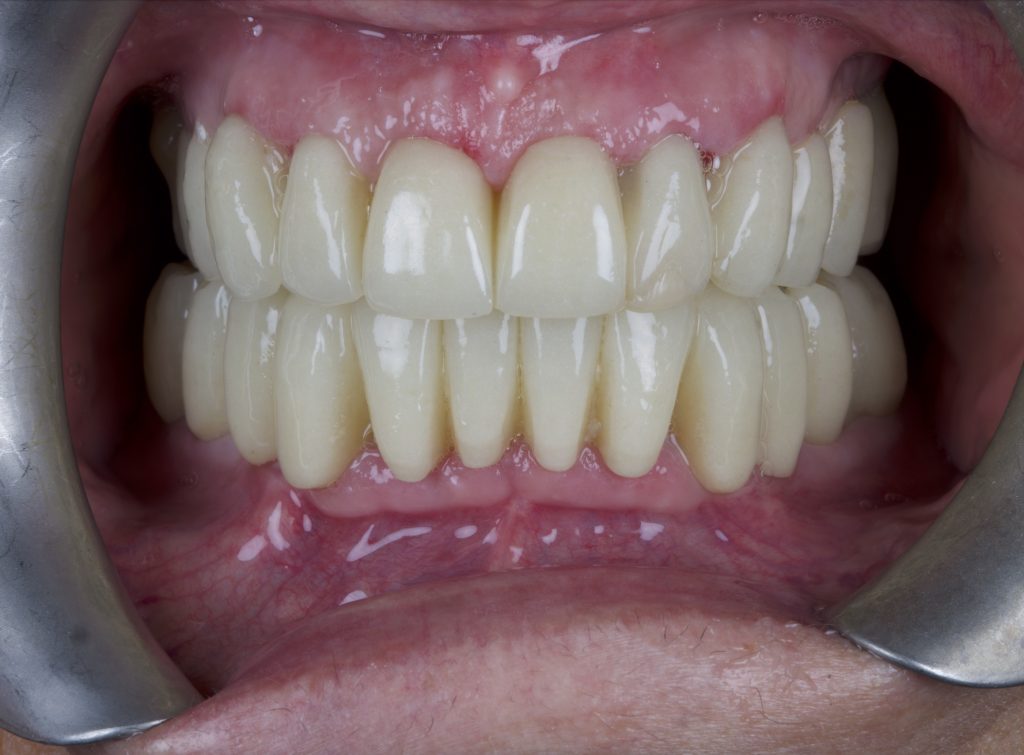

La protesi, realizzata in PMMA multilayer cementata su basi in titanio, è stata avvitata in bocca e regolata in occlusione. I parametri estetici e funzionali, così come erano stati progettati, sono stati riproposti sulla protesi provvisoria immediata.

Le viti protesiche di fissaggio sono state serrate ad un torque di 30N/cm e la paziente è stata controllata a distanza di 1 settimana e poi ogni 3 mesi in attesa di fare un lavoro protesico definitivo (Figure 15-16).